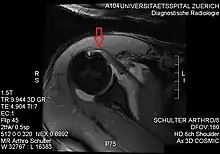

Imaging

There is no singularly imaging device or technique for a satisfying and complete subscapularis examination, but rather the combination of the sagittal oblique MRI / short-axis US and axial MRI / long-axis US planes seems to generate useful results. Additionally, lesser tuberosity bony changes have been associated with subscapularis tendon tears. Findings with cysts seem to be more specific and combined findings with cortical irregularities more sensitive.[5]